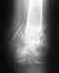

Re: Перелом ладьевидной кости

Надо оперировать. Если есть в пределах досягаемости отделение хирургии кисти - это лучший вариант.